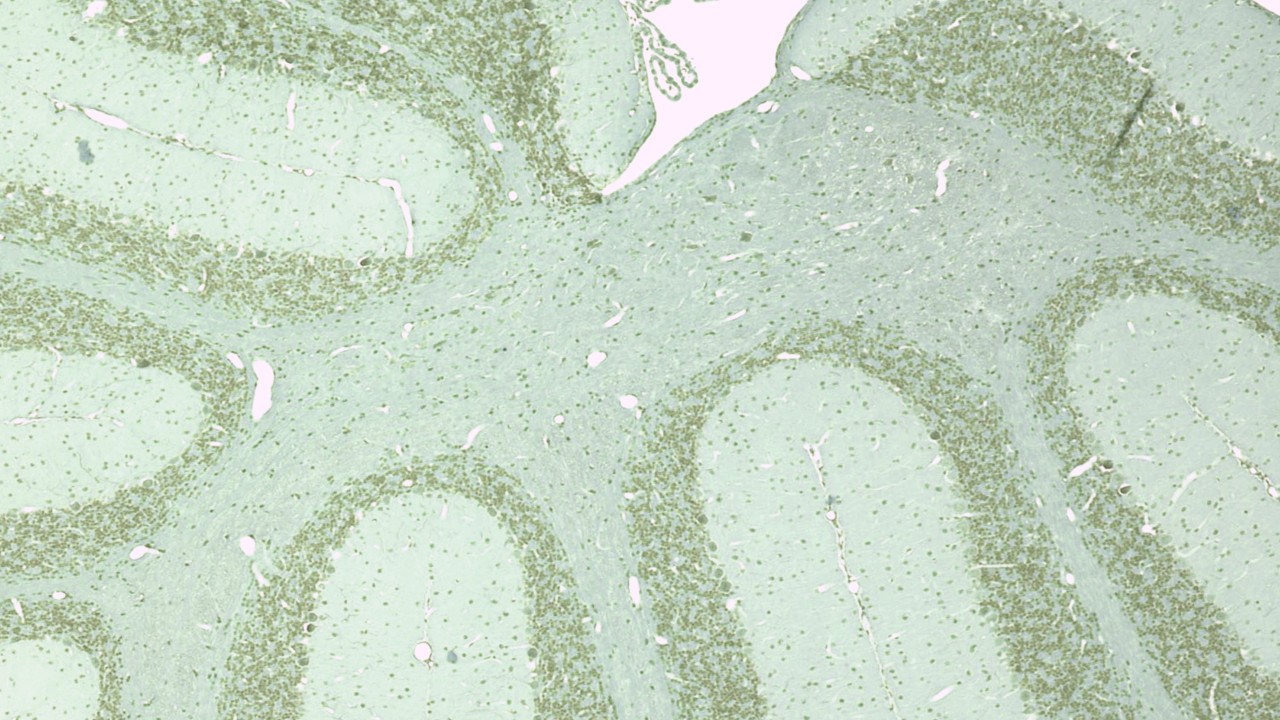

De fysieke werkomgeving hangt af van de functie. Terwijl de veiligheid van een auto binnen de verkoopbranche van belang is, zijn in onze laboratoria en productieprocessen programma's over industriële hygiëne van cruciaal belang om het risico van letsel of ziekte volledig of tot een minimum te beperken.